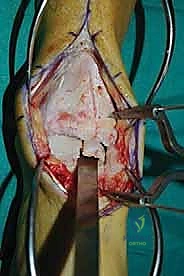

الغوص العميق في جراحة الطعم الخيفي الهيكلي (Structural Allograft Reconstruction)

يهدف هذا الإجراء العبقري إلى استبدال الغضروف والعظم التالفين والميتين بنسيج سليم تماماً مأخوذ من متبرع متوفى (طعم خيفي - Allograft). هذا الطعم يتم تعقيمه وحفظه في بنوك الأنسجة العالمية وفقاً لأعلى المعايير الطبية الصارمة لضمان خلوه من أي أمراض معدية والحفاظ على حيوية الخلايا الغضروفية.

- الترميم التشريحي الحقيقي: يسمح باستعادة الشكل الهندسي الدقيق لعظم الكاحل، بما في ذلك المنحنيات المعقدة لكتف التالوس.

- توفير غضروف طبيعي (Hyaline Cartilage): الغضروف المزروع هو غضروف زجاجي طبيعي،